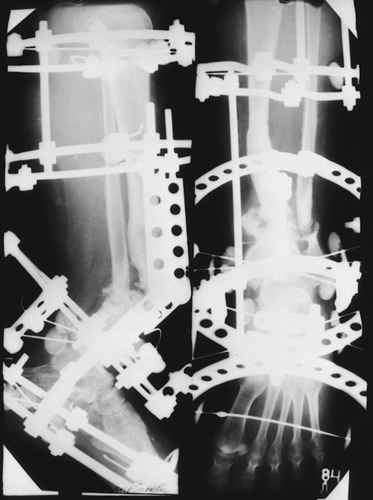

Случай, который я представляю, был сделан мной около 20 лет назад в Кургане.

Женщина 28 лет, пошедшая 13 предыдущих оперативных вмешательств по-поводу ВПБ имела 9 см. укорочения.

На первом этапе аппаратом Илизарова закрыто устранена деформация голени.

На втором этапе произведёно освежение краёв костных фрагментов б/б и м/б костей с приданием проксимальному фрагменту б/б кости впалой, а дистальному выпуклой формы, открытие канала проксимального фрагмента и погружной остеосинтез, а также остеотомия б/б кости в в/3 и м/б кости на границе с/3 и н/3 голени. Больной проводился одновременный бифокальный компрессионно-дистракционный остеосинтез. Достигнуто 11 см. удлинение и сращение ВПГ.

Срок лечения 11 месяцев. Наблюдение 2 года.